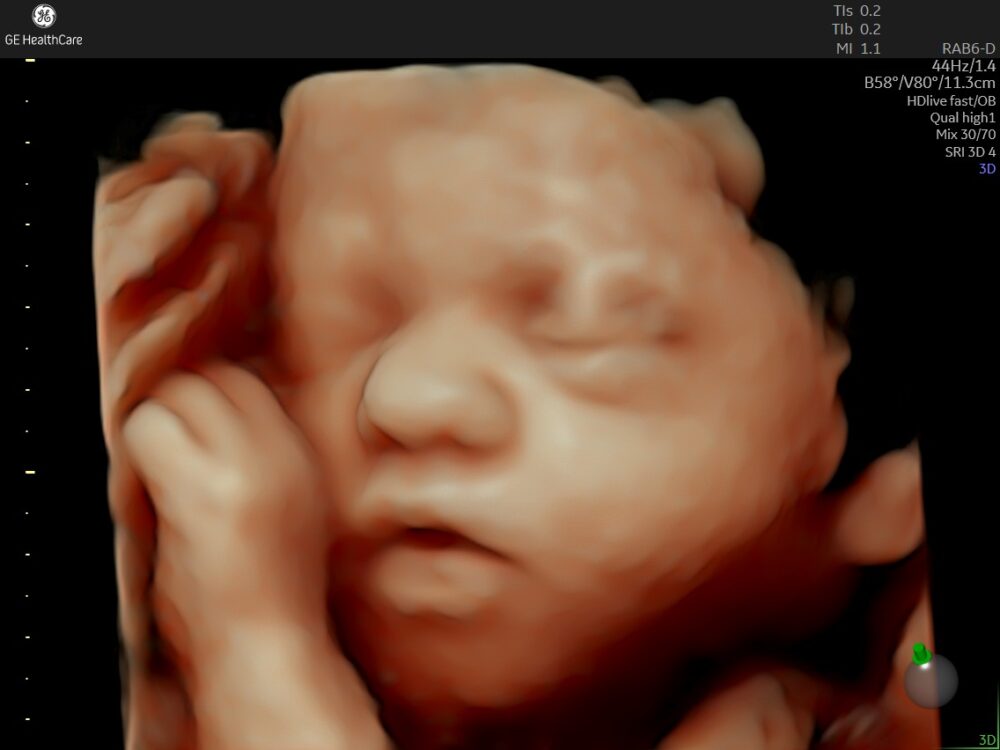

ご希望の方に3D/4Dエコーが可能(別途料金がかかります。詳細はこちらをご覧ください)

他の病院で妊婦健診中の方も、3D/4Dエコーのみでの受診が可能です

当院では、ご希望の方に最新の超音波機器で3D/4Dエコーが行えます(別途料金)。その時にしか見えないお腹の赤ちゃんを、立体的にご覧いただけますので、楽しいお時間をお過ごしいただけると嬉しいです。